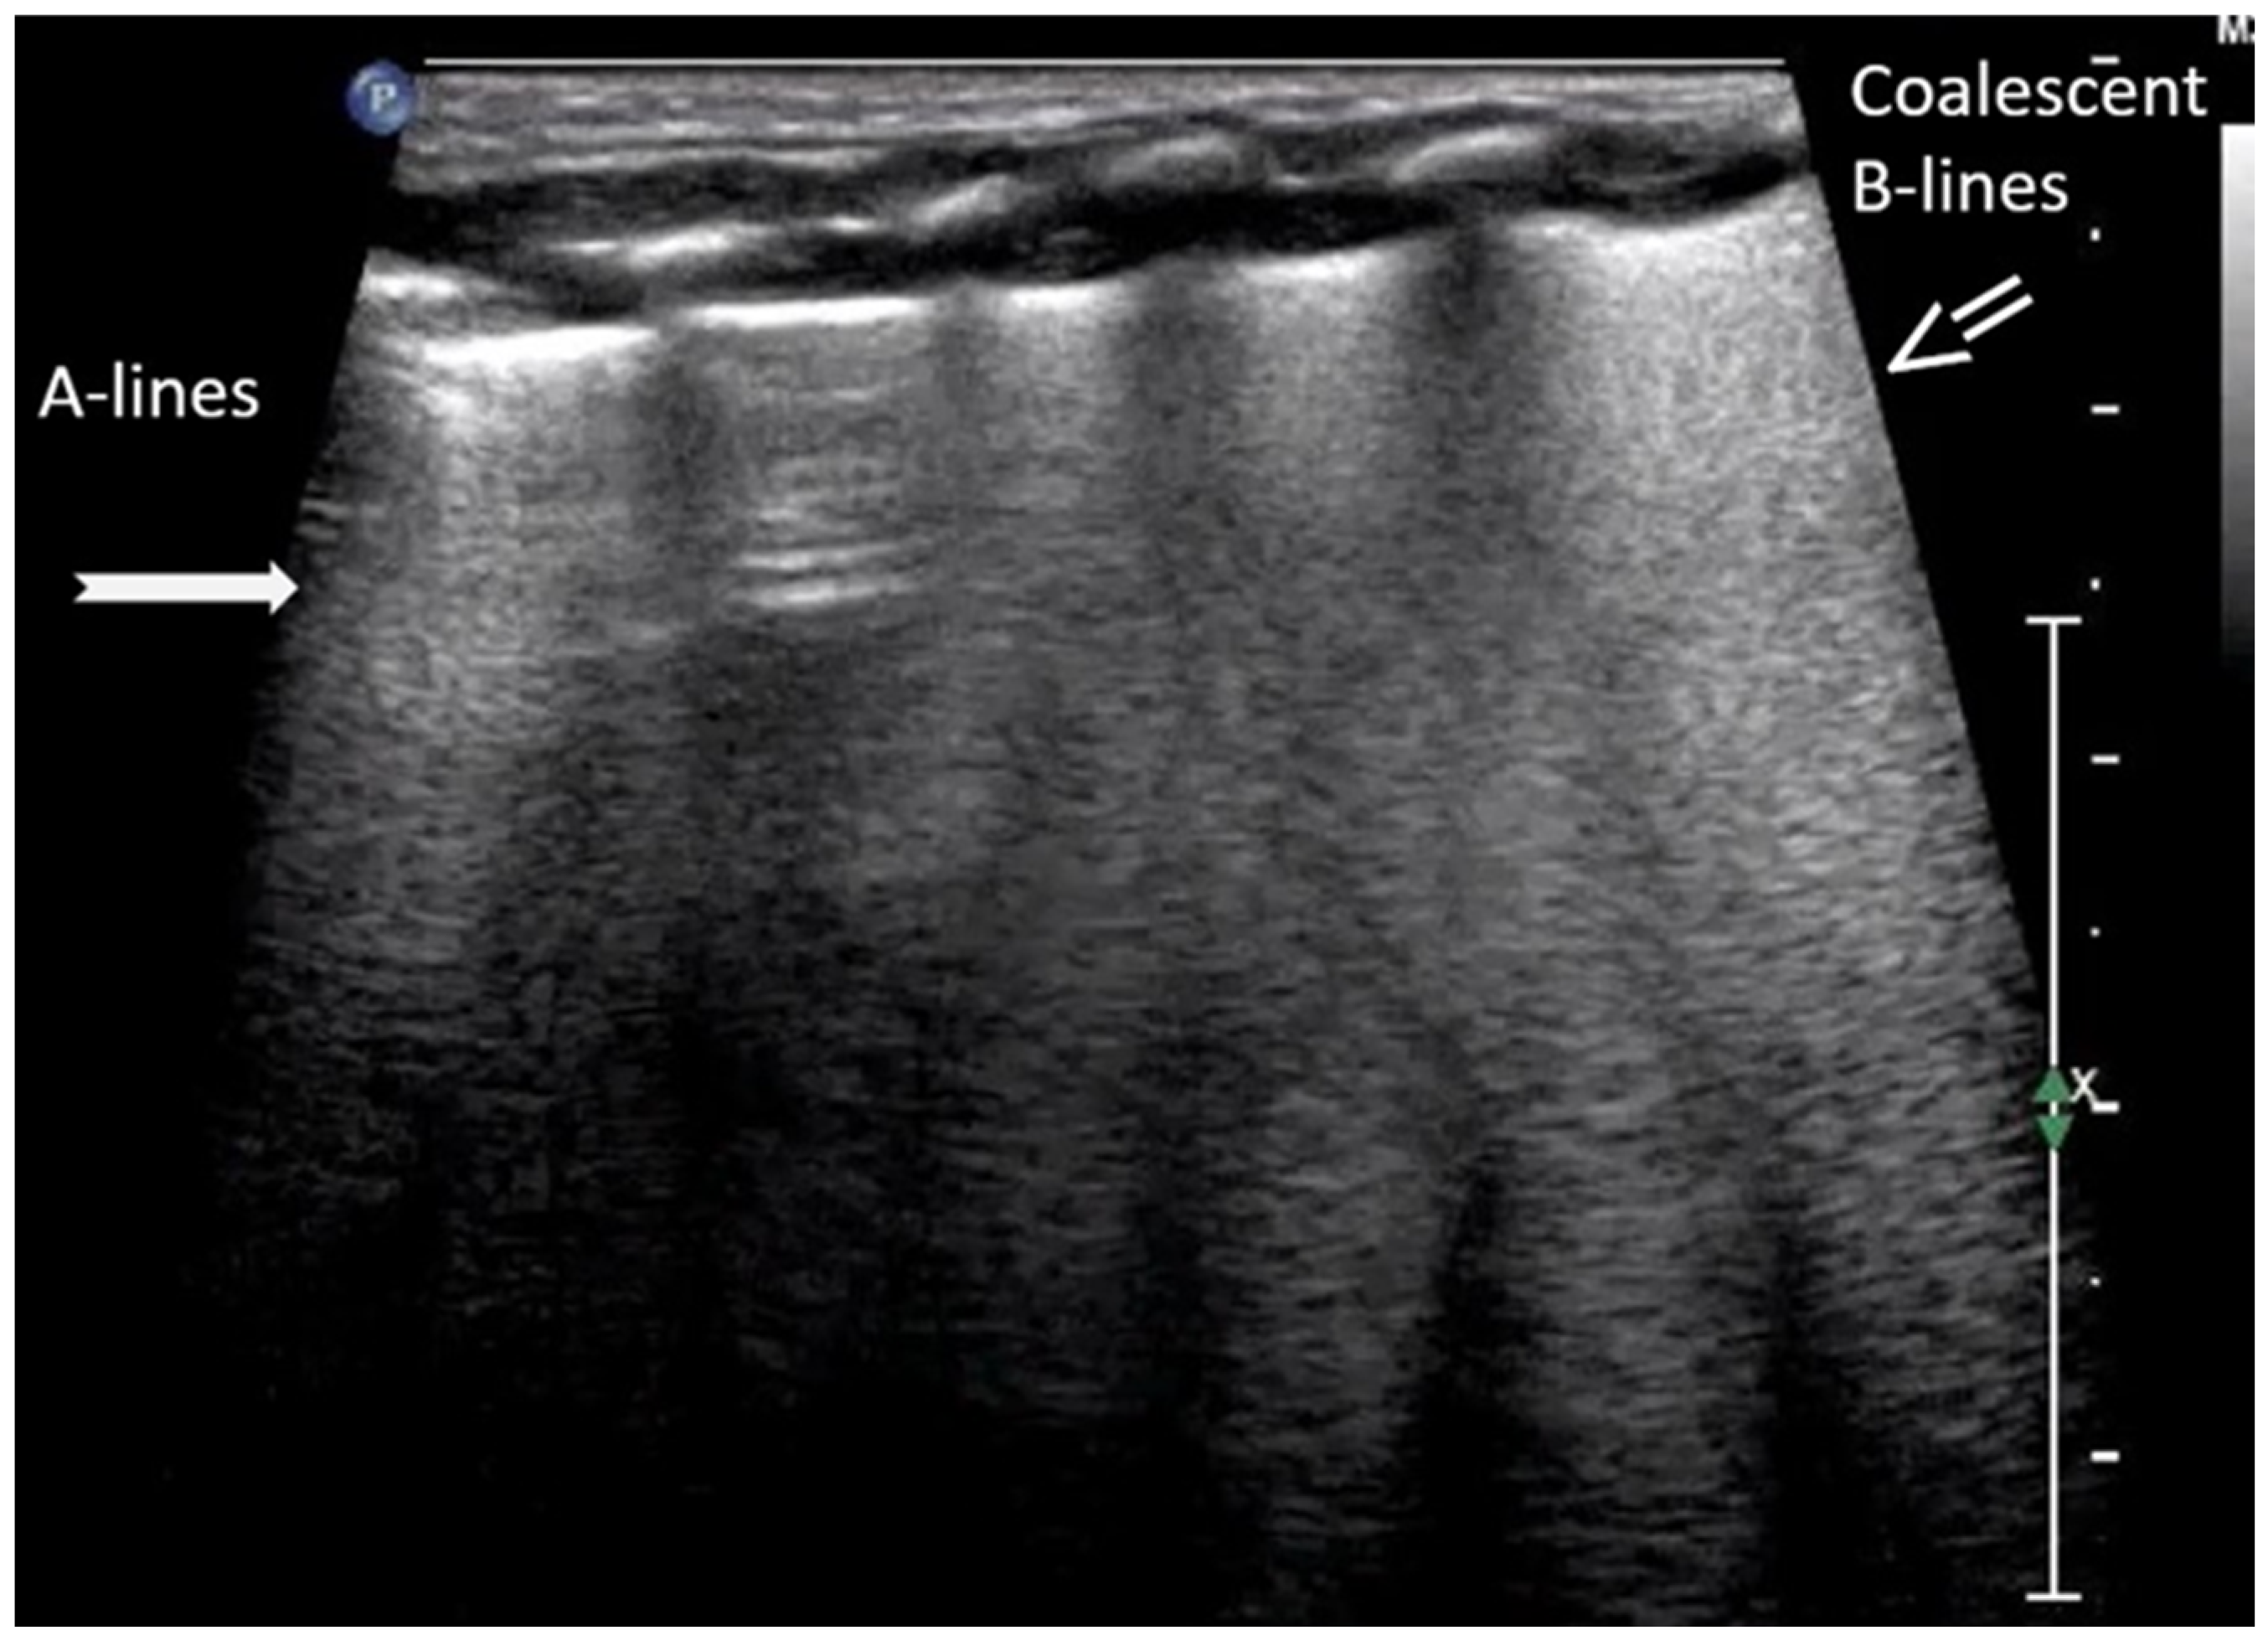

A-lines are horizontal, bright, echogenic lines that appear at equal intervals below the pleural line, running parallel to it (Figure 1). They are reverberation artifacts caused by the reflection of ultrasound waves between the pleura and the ultrasound probe. Although their presence typically indicates well-aerated, healthy lung tissue, A-lines can also be seen in certain pathological conditions, such as pneumothorax, where free air is present. Thus, A-lines are not always necessarily a sign of normal, healthy lungs [5,6,12,13,14,15,16].

Figure 1.

A-lines: Horizontal, bright, echogenic lines at equal intervals below the pleural line, running parallel to it. A-Lines are one of the main (basic) artifacts in LUS.

The “lung point” or “lung point sign” is a highly specific lung sonographic sign which helps in the diagnosis of pneumothorax and can also facilitate the assessment of pneumothorax severity. In particular, the severity of pneumothorax depends on its position relative to the anatomical lines that define the regions of the chest. In LUS, the “lung point” is defined as the boundary between the area without normal lung sliding (i.e., pneumothorax) and the area where normal lung sliding is present (normal lung) (Figure 8) [4,12,15,16,25,26].

Figure 8.

Lung point sign: The transition point between the aerated lung with coalescent B-lines (which probably represents respiratory distress syndrome) which are absent in pneumothorax and the area with A-lines (transparent arrow) but without lung sliding (absent in pneumothorax in real-time scanning).